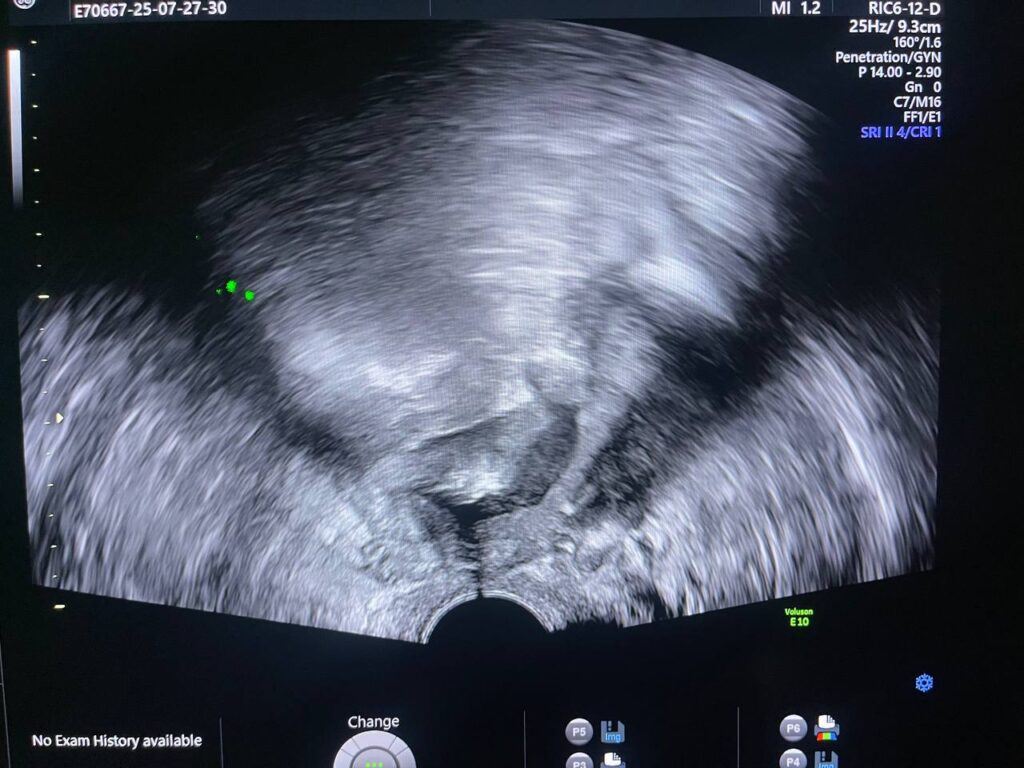

Post Hystercetomy Abcess Formation

Uterus removed , with presence of collected heterogenous fluid 27x14mm in the bed , contain air , could be abscess ? please for further study to exclude other pathology